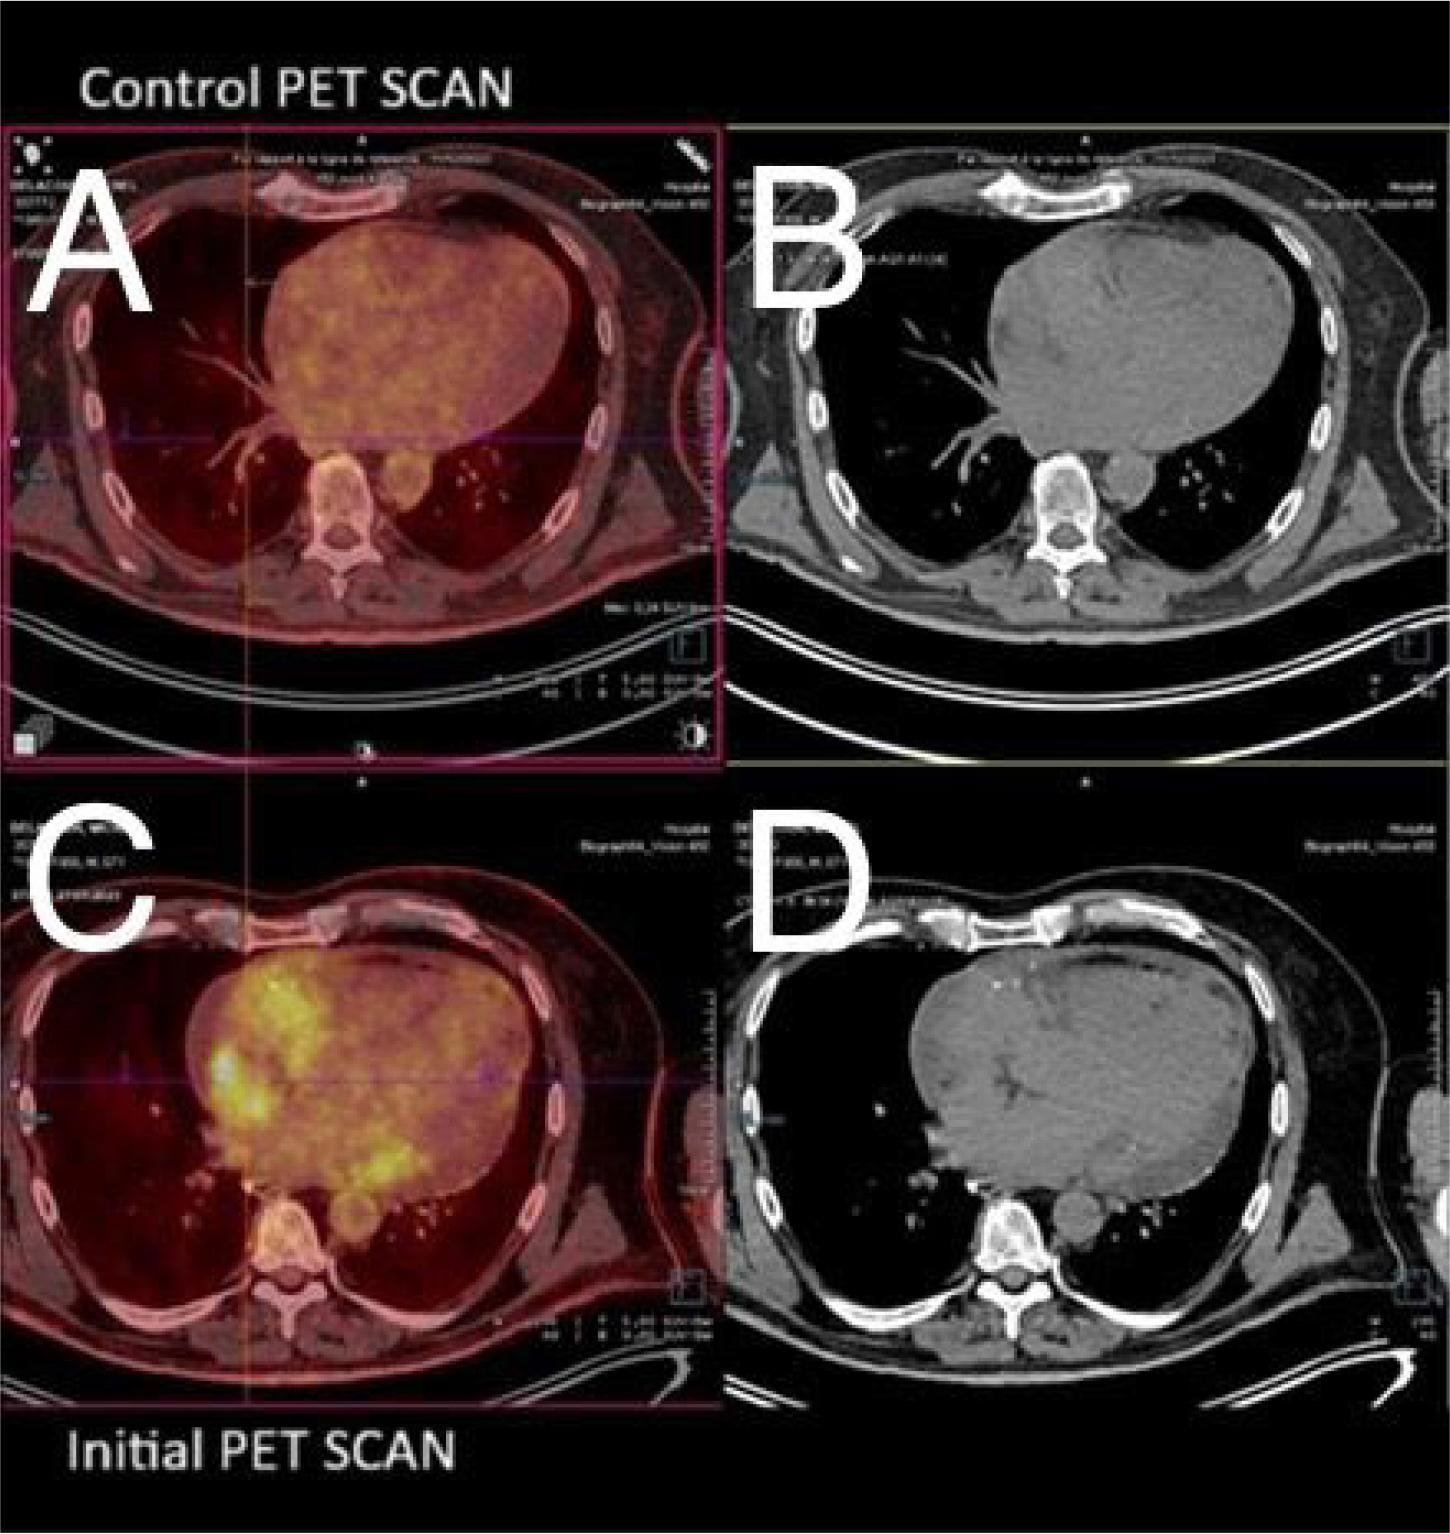

Figure 3.